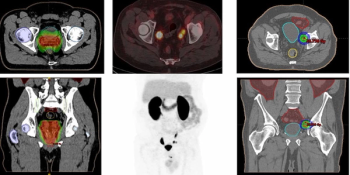

In an analysis of patients with intraprostatic/prostate bed findings of biochemical prostate cancer recurrence, the use of 18F-DCFPyL PET/CT led to an 82.3 percent cancer detection rate in comparison to 80 percent for multiparametric MRI, according to research presented at the recent Society for Nuclear Medicine and Molecular Imaging (SNMMI) conference.